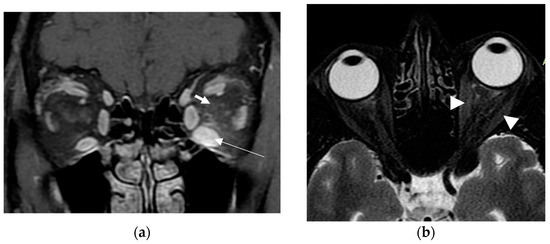

2. Case Presentation